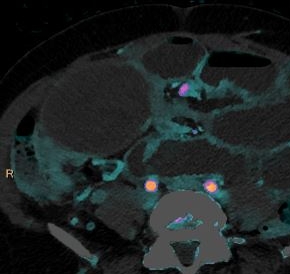

Myocardial infarction

Gopal Punjabi

March 15, 2018